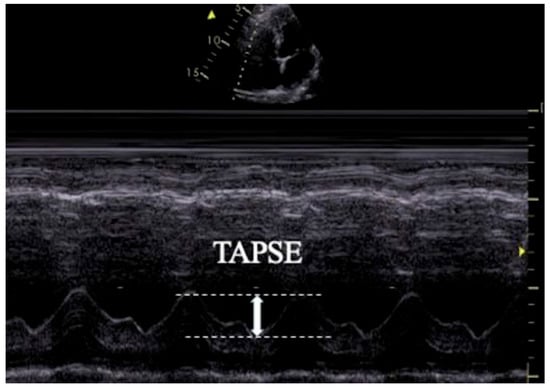

TAPSE was measured in the apical four-chamber view by placing an M-mode cursor across the tricuspid annulus and recording the peak systolic longitudinal displacement. The average value of five consecutive cardiac cycles was documented (Figure 1).

Figure 1. Transthoracic echocardiographic image illustrating TAPSE measurement.